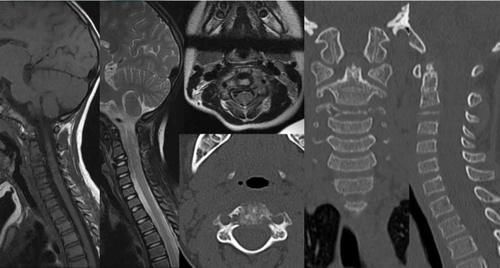

文章插图